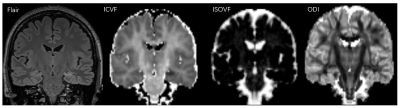

Fig. 1. Images from a 29-year-old woman with left hippocampal sclerosis.

Fifty-nine unilateral TLE-HS and 64 healthy controls (HC) were retrospectively enrolled. The diagnosis of TLE-HS based on a comprehensive evaluation, including detailed clinical history, seizure semiology, neurological examination, scalp video-EEG recordings, and MRI assessment. All patients met the following inclusion criteria: 1) unilateral temporal lobe seizure onset through scalp or intracranial video EEG recordings; 2) MRI evidence of pathology located within the epileptogenic mesial temporal lobe, with hippocampal sclerosis ; 3) concordant PET finding of hypometabolism in the interictal temporal lobe. All controls were free of neurological or psychiatric illnesses, and had no structural abnormalities on MRI images. For all participants, MR images were acquired on a 3T MR scanner (MAGNETOM Prisma, Siemens Healthcare, Erlangen, Germany). DWI data were acquired using a single-shot spin echo EPI sequence (b-values of 0, 1000, 2000 s/mm2, 30 diffusion sampling directions for each non-zero b value, TR = 3800ms, TE = 72ms, 60 axial slices with 2.2 mm thickness and 2 mm gap, matrix size = 110 × 110, field of view = 220 × 220 mm2, voxel size = 2.0 × 2.0 × 2.2 mm3, and scan time, 3min:32s. Eddy current and motion correction were conducted on DWI images using the Diffusion Kit Eddy tool (http://diffusionkit.readthLedocs.io). Then the NODDI parameter fitting was performed using an open source Amico tool (https://github.com/daducci/AMICO/), and the parametric maps of Isotropic volume fraction (ISOVF), intracellular volume fraction (ICVF), and orientation dispersion index (ODI) were obtained. Both MR Fluid Attenuated Inversion Recovery (Flair) images and T1 MPRAGE images from each subject were co-registered to diffusion weighted images using the ITK-SNAP (http://www.itksnap.org) software, and bilateral hippocampal segmentations were saved as the segmented regions of interest (ROIs) by consensus two neuroradiologists. Then, the mean values of parameters of NODDI and signal intensity of Flair image for hippocampal segmentations. One-way analysis of variance (ANOVA) or Kruskal-Wallis ANOVA were used to detect differences in parameters among ipsilateral, contralateral and HC groups. Then two sample t test with LSD post-hoc multiple correction method or Mann⁃Whitney U test was used for pairwise comparison between any two groups. And the differential diagnostic efficiency of each parameter was determined by ROC analysis.